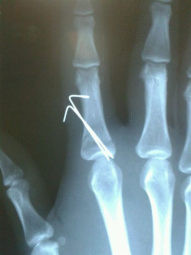

Fractura Dedos de la Mano